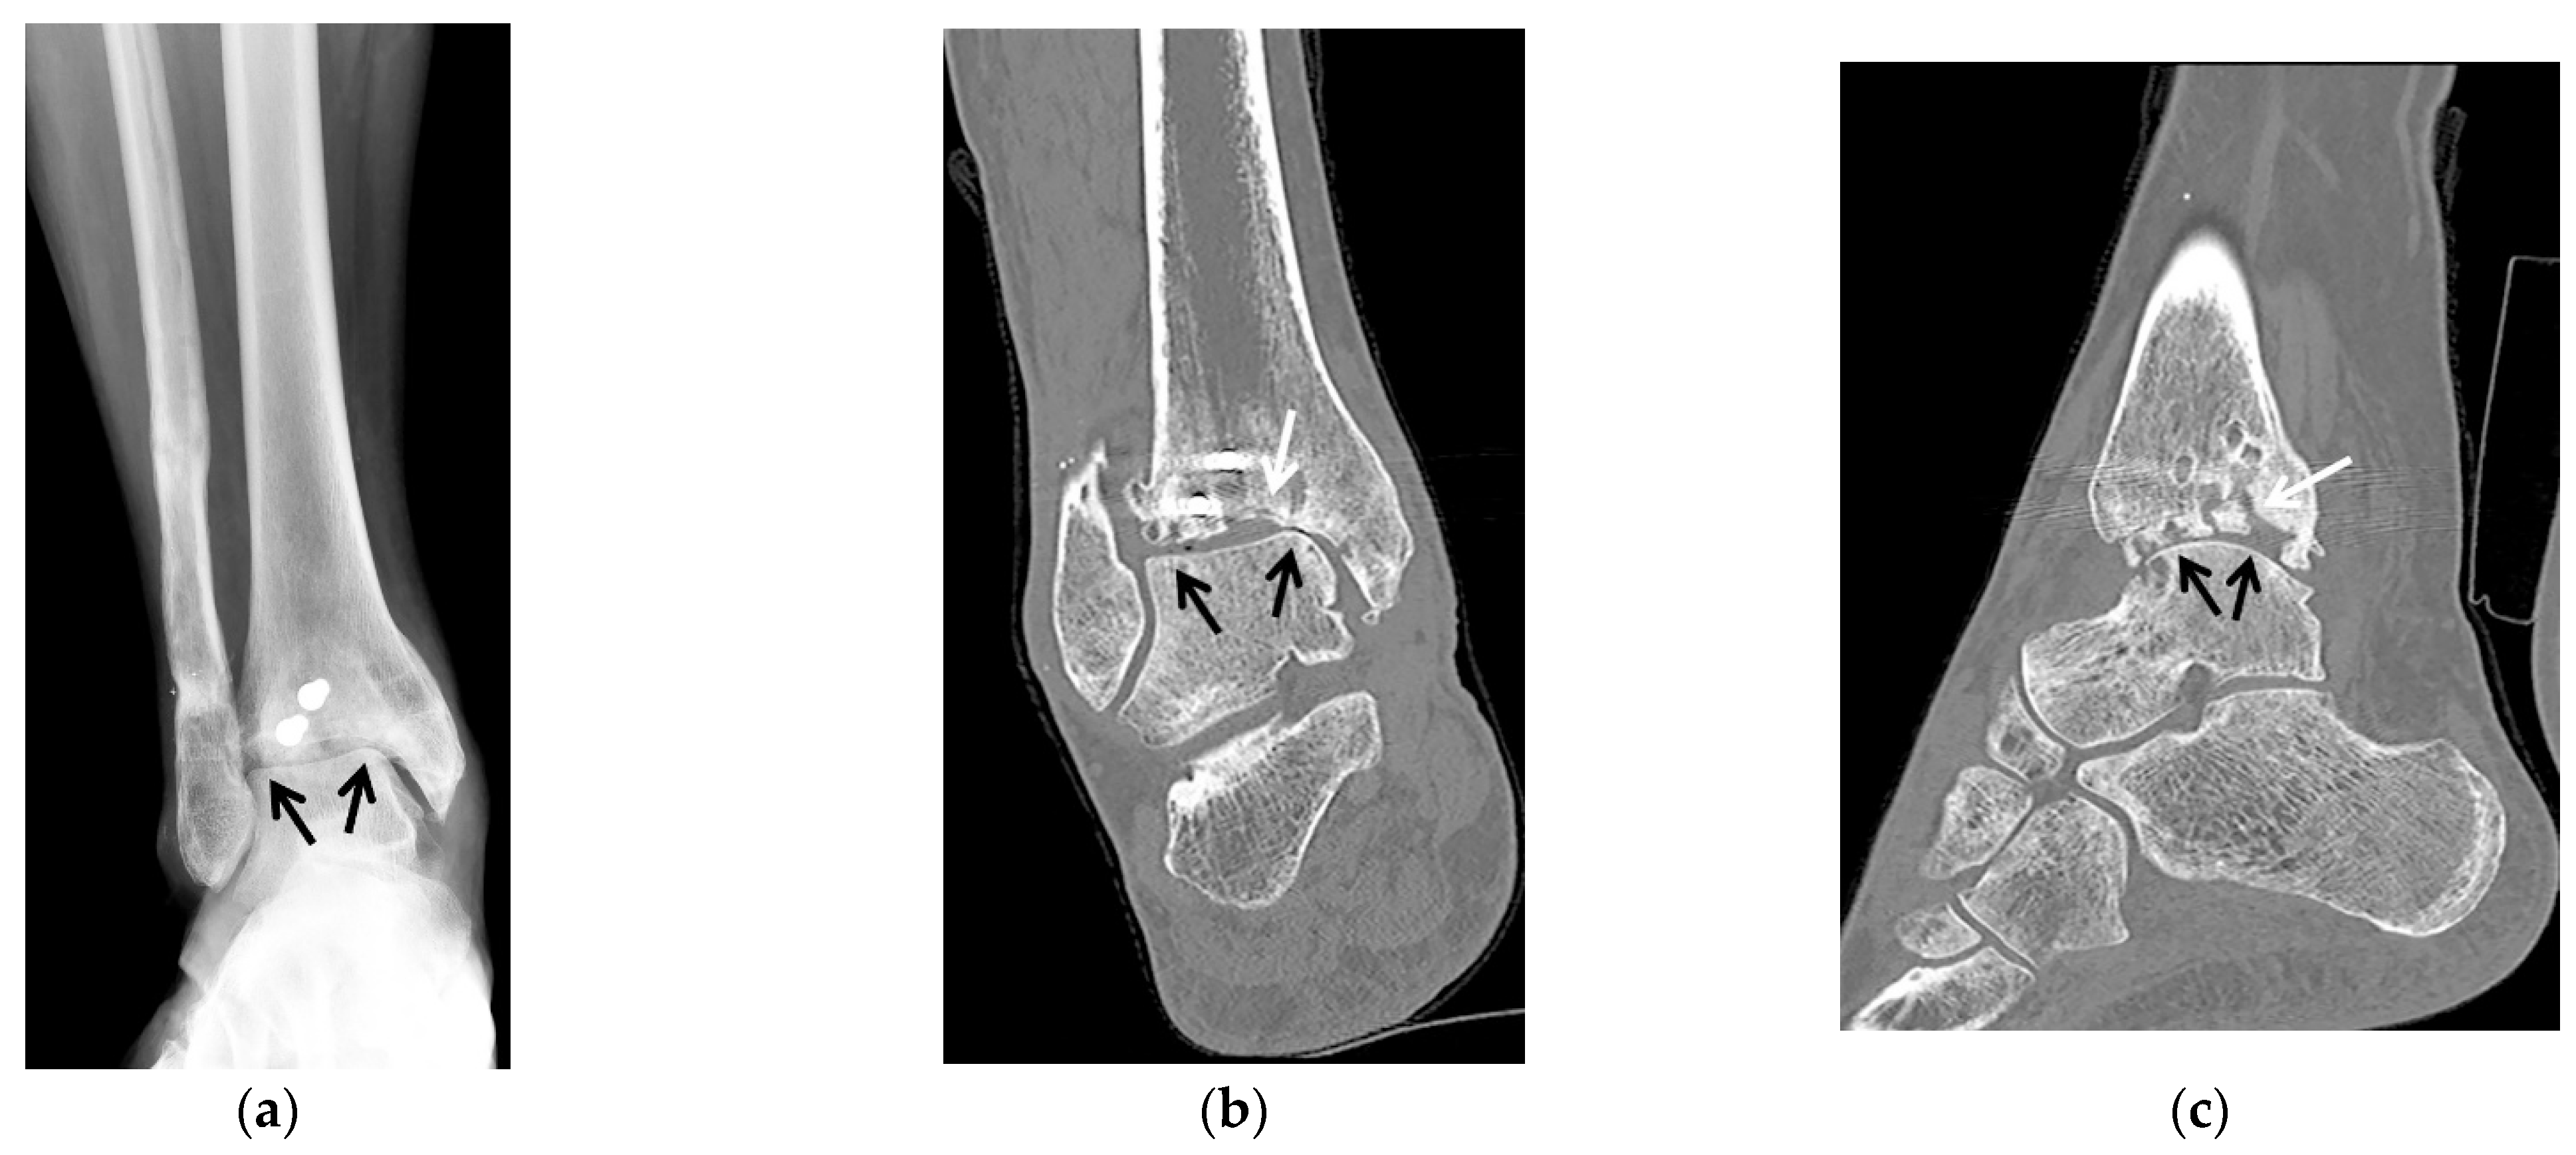

5.2.3. Ankle Arthroplasty